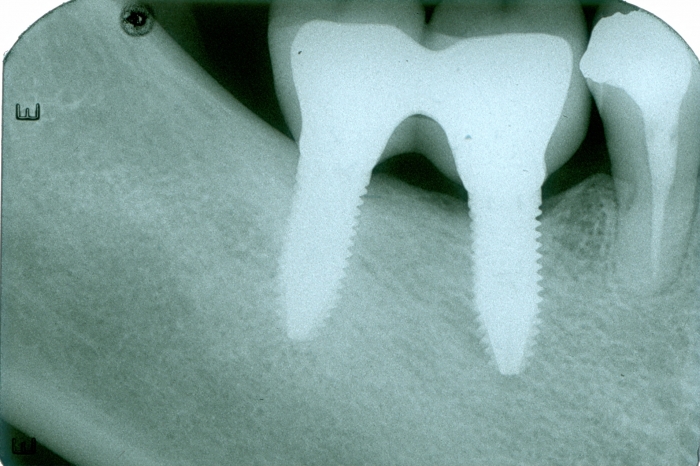

Imagens com prótese fixa em porcelana sobre implantes do caso finalizado em janeiro de 2009